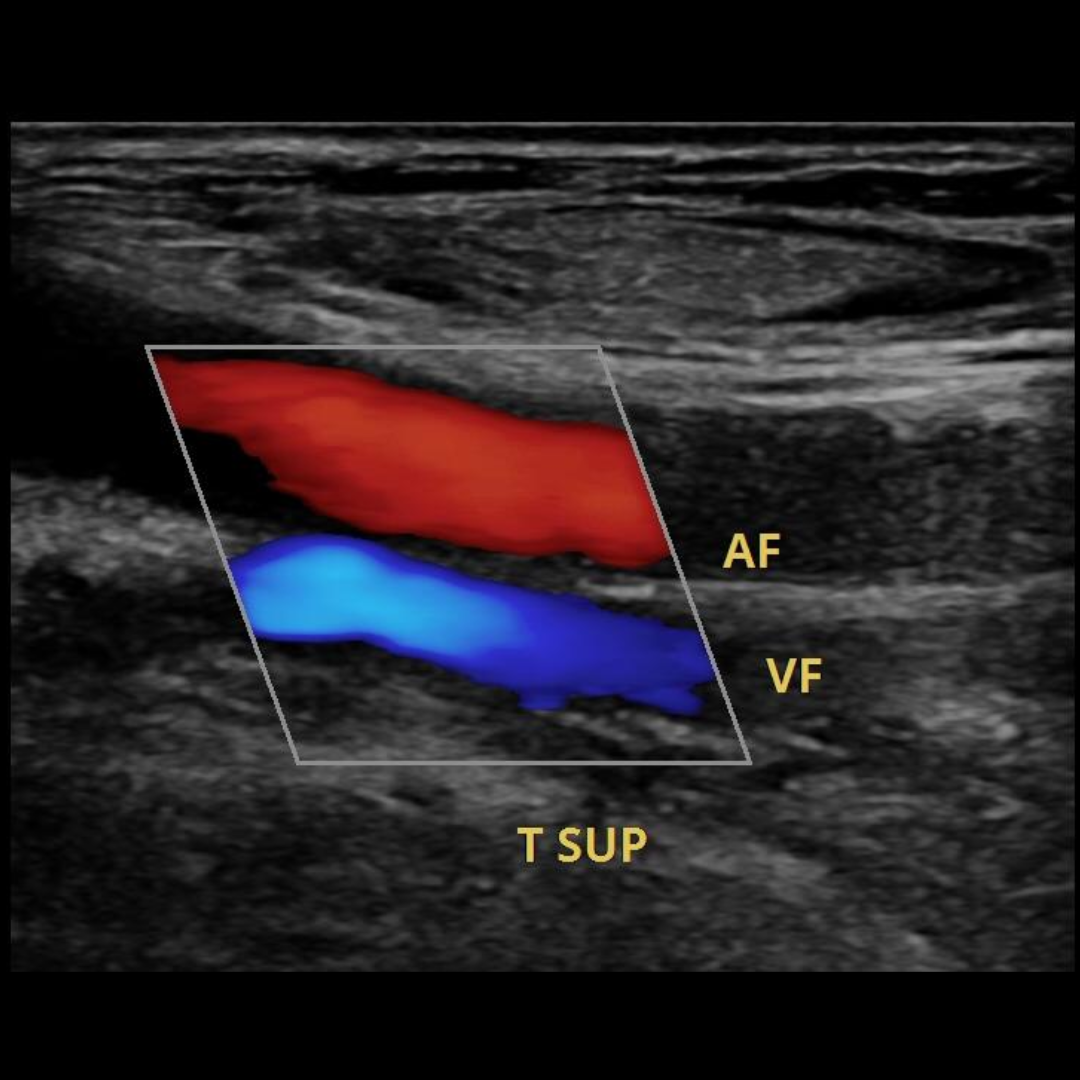

Ecografía Doppler Venoso

La ecografía Doppler Venoso es un estudio importante que permite evaluar las venas de miembros superior e inferiores, y permite evidenciar la presencia válvulas venosas insuficientes que condicionen varices, así como obstrucciones venosas en la trombosis venosa profunda.